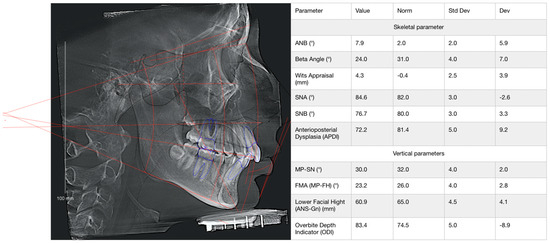

| Sections of the Jaw | Group 1 (n = 19), HU | Group 2 (n = 19), HU | Group 3 (n = 19), HU | Group 4 (n = 19), HU |

|---|---|---|---|---|

| Anterior mandible | 2790 [2200; 3010] 1,3 | 989.0 [940.0; 1122] 1,3,4 | 1749 [1570; 1999] 1,2,4 | 3096 [1980; 3554] 2,3 |

| Posterior mandible | 1560 [1200; 1770] 2,3 | 785.0 [690.0; 916.0] 1,4 | 850.0 [790.0; 940.0] 1,4 | 1800 [1384; 1960] 2,3 |

| Anterior maxilla | 534.5 ± 123.4 | 476.3 ± 71.3 4 | 460.5 ± 66.2 4 | 614.6 ± 171.7 2,3 |

| Posterior maxilla | 378.9 ± 91.0 2 | 207.9 ± 19.4 1,3,4 | 302.5 ± 104.7 2,4 | 432.5 ± 114.6 2,3 |